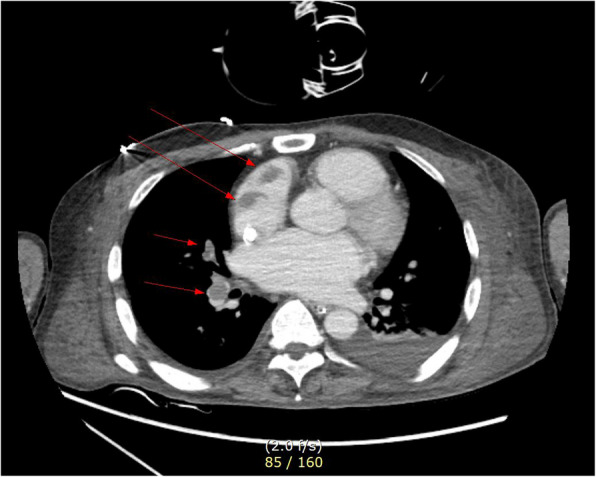

Case presentation: A 44-year-old man presented to our hospital with complaints of palpitations. He had a recent history of coronavirus disease of 2019 (COVID-19) infection, which may have exacerbated undiagnosed hyperthyroidism, leading to thyroid storm and cardiogenic shock (left ventricular ejection fraction [LVEF], 13%). Heart failure improved with immediate medical management and V-A ECMO for 4 days, resulting in LVEF, 30%. V-A ECMO provide both respiratory and cardiac support, allowing myocardial recovery. Although the patient's cardiac output improved, uncontrolled tachycardia persisted. Medical treatment for hyperthyroidism-associated tachycardia was continued after V-A ECMO weaning but failed to achieve adequate rate control. Ten days after weaning V-A ECMO, the patient suddenly developed pulmonary thromboembolism and hypoxia despite ongoing heparinization. To manage refractory hypoxia, V-V ECMO was initiated, as it exclusively provides respiratory support. Given that persistent TS was the underlying cause of the patient's instability, we proceeded with thyroidectomy under general anesthesia with V-V ECMO support, despite the associated risks. On postoperative day 4, the patient was successfully weaned off V-V ECMO. By postoperative day 18, he was discharged without complications, with an improved LVEF of 52.5%.